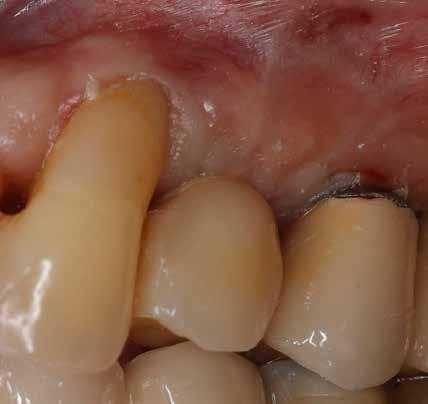

A 2020 januárjában elkezdett kezeléssorozat befejezését az év márciusában, hazánkba is begyűrűző Covid-19 pandémia késleltette, így kb. 6 hónap gyógyulás után láttunk hozzá az emergencia profil és a gingivális zenit ideiglenes koronával történő formázásához (11. és 12. kép). A 3 hetente végzett apró alakításokkal sikerült megfelelő ínyprofilt kialakítani, a „rózsaszín esztétika” a páciens számára is megfelelő volt. A bal felső nagymetsző fog meziális kompozit tömés cseréjét követően, individualizált nyitott kanalas lenyomati fejet készítettünk: az akrilát ideiglenes korona profilját átlátszó szilikonnal lemásoltuk, majd a körszimmetrikus gyári lenyomati fej és az ideiglenes korona kontúrja közötti hézagot folyékony kompozittal töltöttük ki (13. kép). Az így készített egyéni lenyomati fejjel vettünk lenyomatot a végleges, kerámialeplezésű cirkónium-dioxid vázas, átmenő csavaros rögzítésű koronához. (A fogtechnikai munkát Nébl Péter fogtechnikusmester készítette.), (14., 15., 16 és 17. képek).

A kész korona átadásakor a páciens elégedett volt az esztétikával, az azóta eltelt évben rendszeres kontrollokon jelent meg, melyek során meggyőződtünk a kemény- és lágyszövetek stabilitásáról (18. és 19. képek).

17. a–b képek: A kész munka átadáskor. 18. a–c képek: 1 éves kontroll. 19. kép: Intraorális kontroll röntgen felvétele 1 évvel az átadás után.